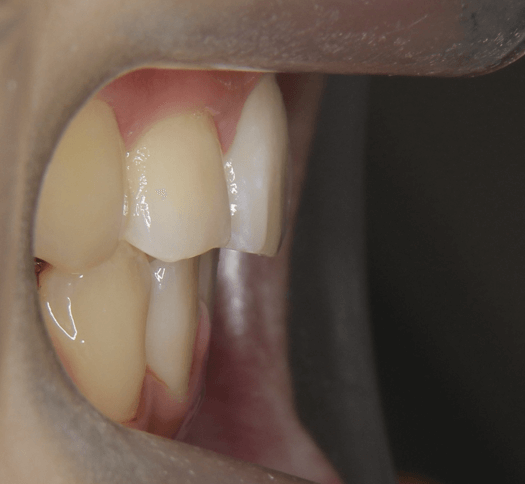

| 年齢・性別 | 11歳1ヶ月の女性 |

|---|---|

| 主訴 | 口元の突出感と歯並びが気になり、将来的な咬合状態を整える目的で来院された患者様です。 |

| 治療期間・回数 | 2年6ヶ月・25回 |

| 費用 | 720,000円 |